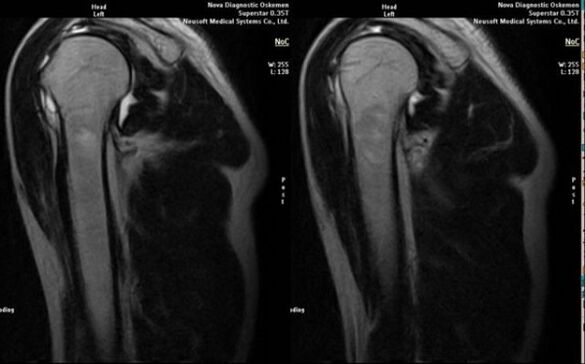

Hlavnou diagnostickou metódou na detekciu deformujúcej sa artrózy ramenného kĺbu je jednoduchá rádiografia.

- magnetická rezonancia a počítačová tomografia;

K príznakom indikujúcim rozvoj artrózy priamo patrí objavenie sa výrazného zúženia kĺbovej štrbiny, skleróza podchrupkových štruktúr, stenčenie samotnej vrstvy chondrocytov, výskyt osteofytov a usadzovanie kryštálikov soli v intraartikulárnej tekutine.